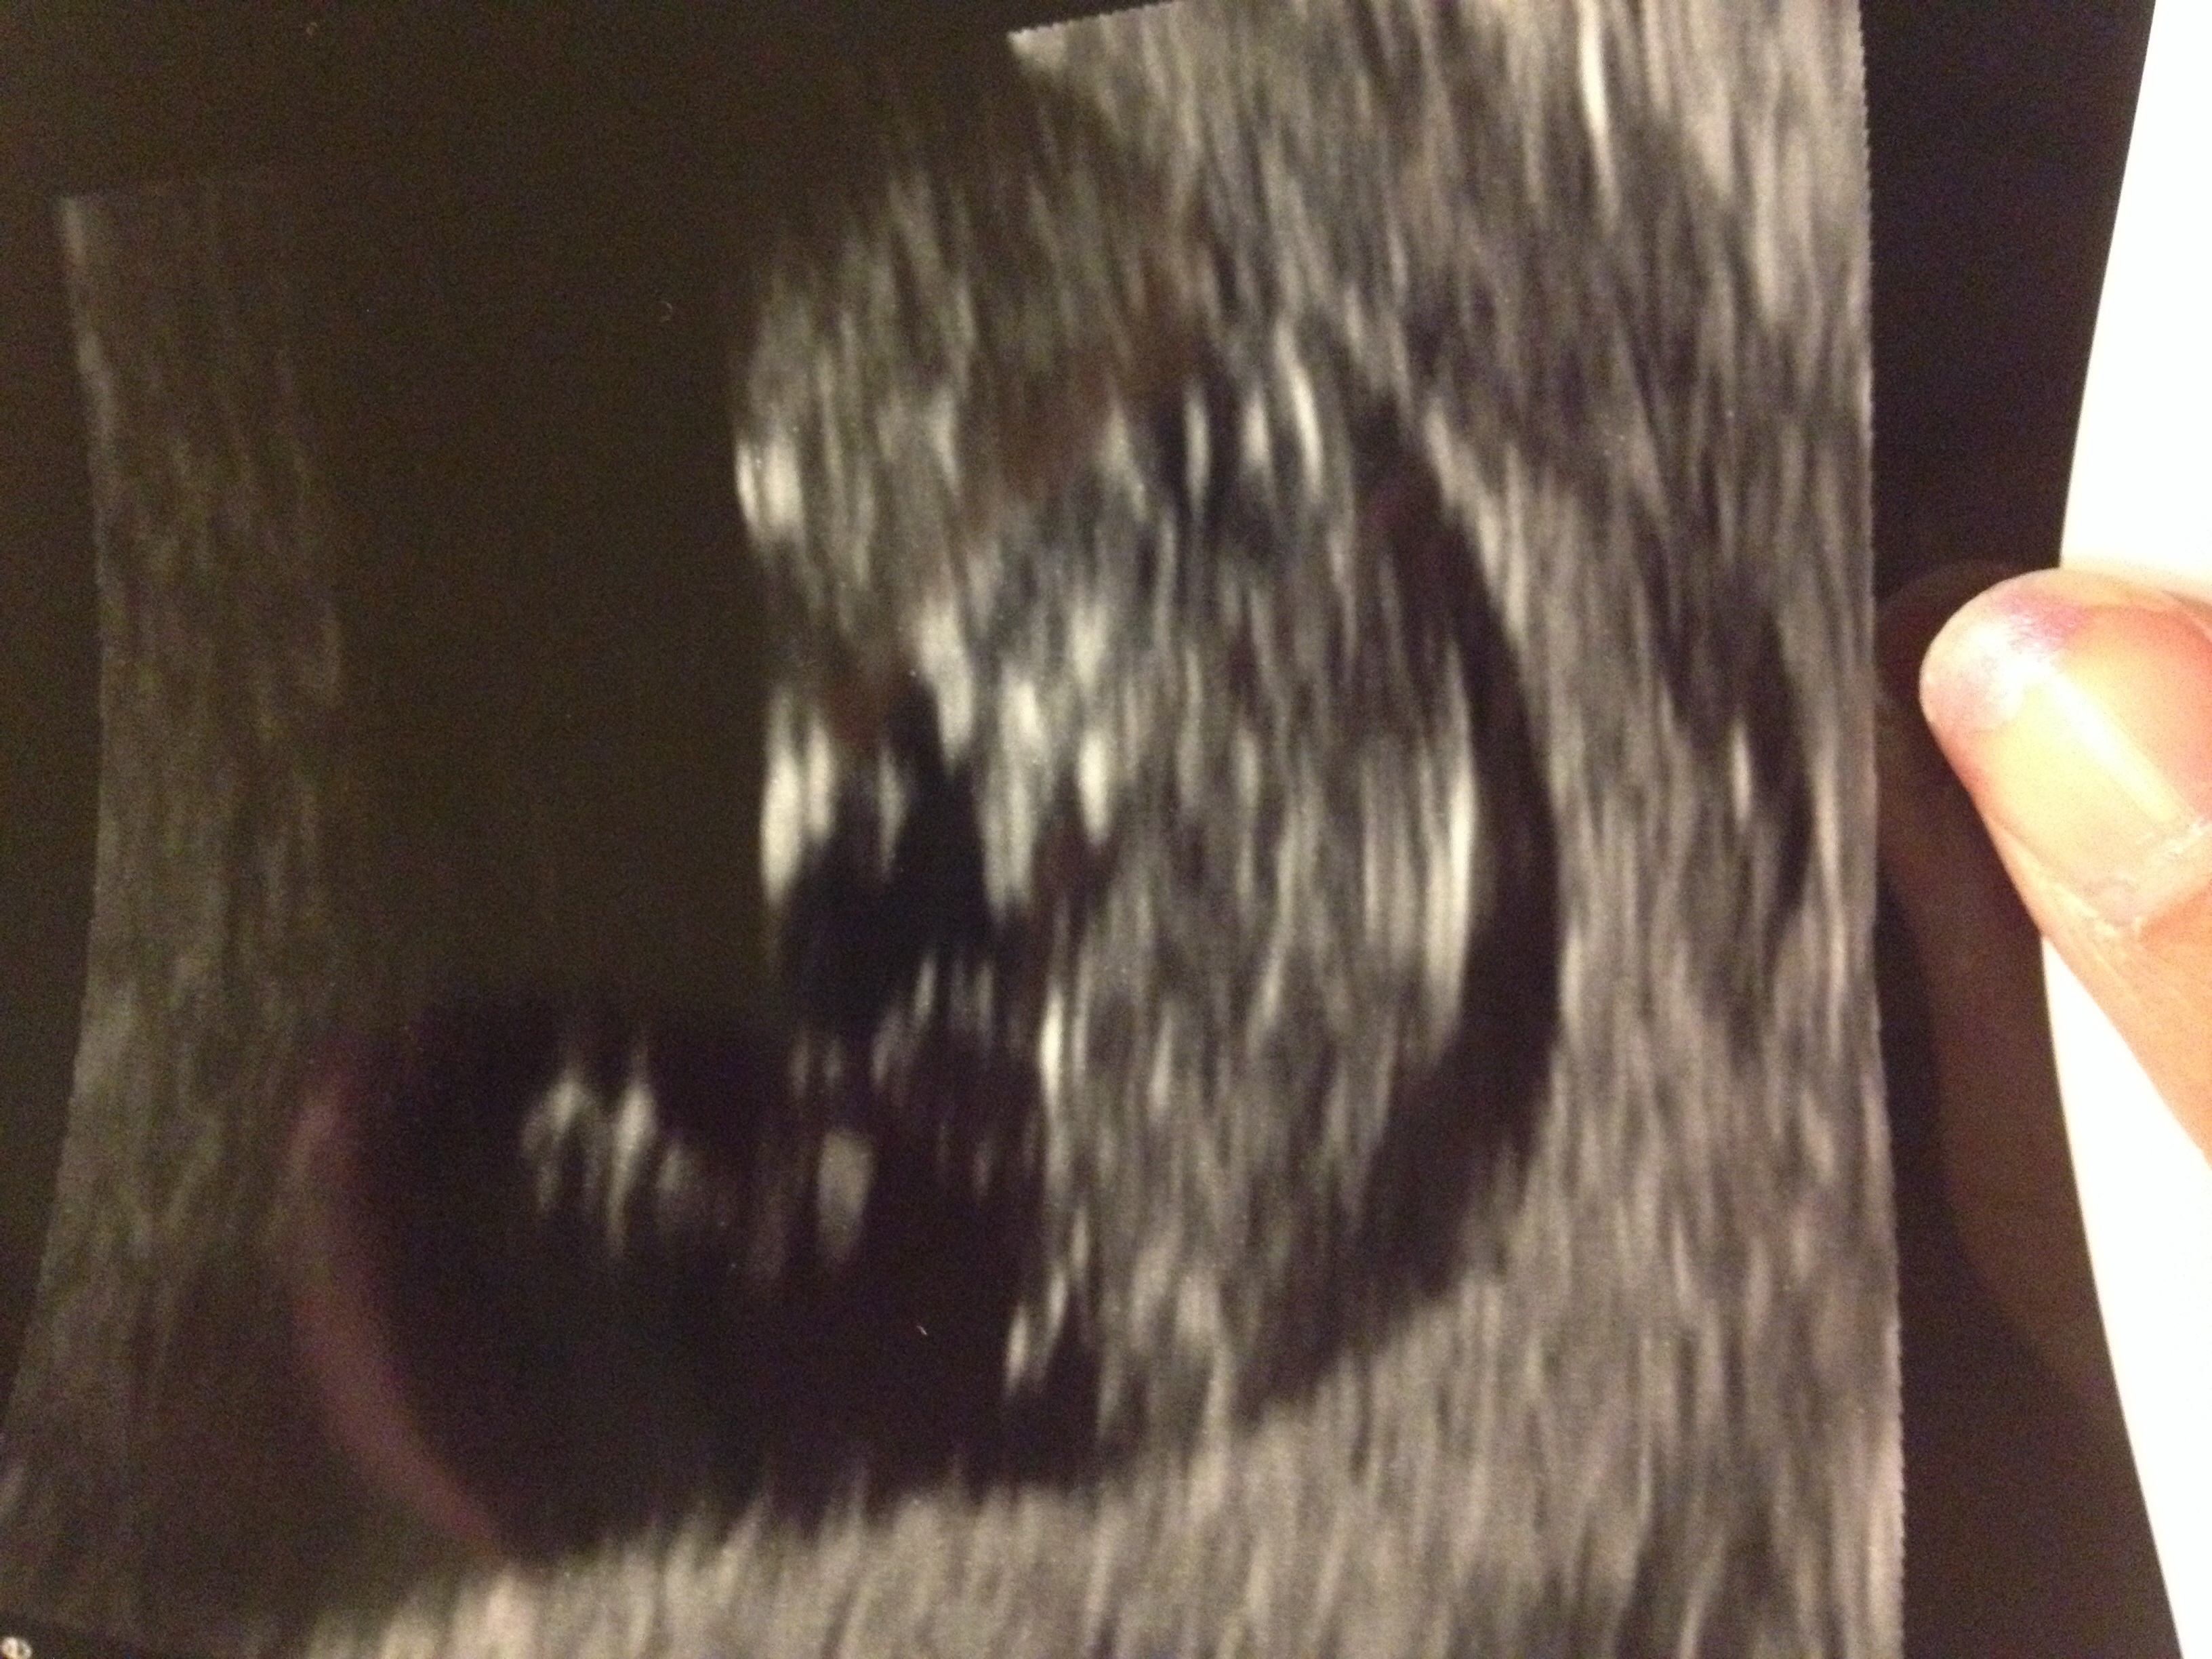

It's a girl!Attachment 19787

YAY! SO EXCITED FOR YOU!!!!

Congratulations!!

Thank you! I'm so scared to let myself believe it's really true!